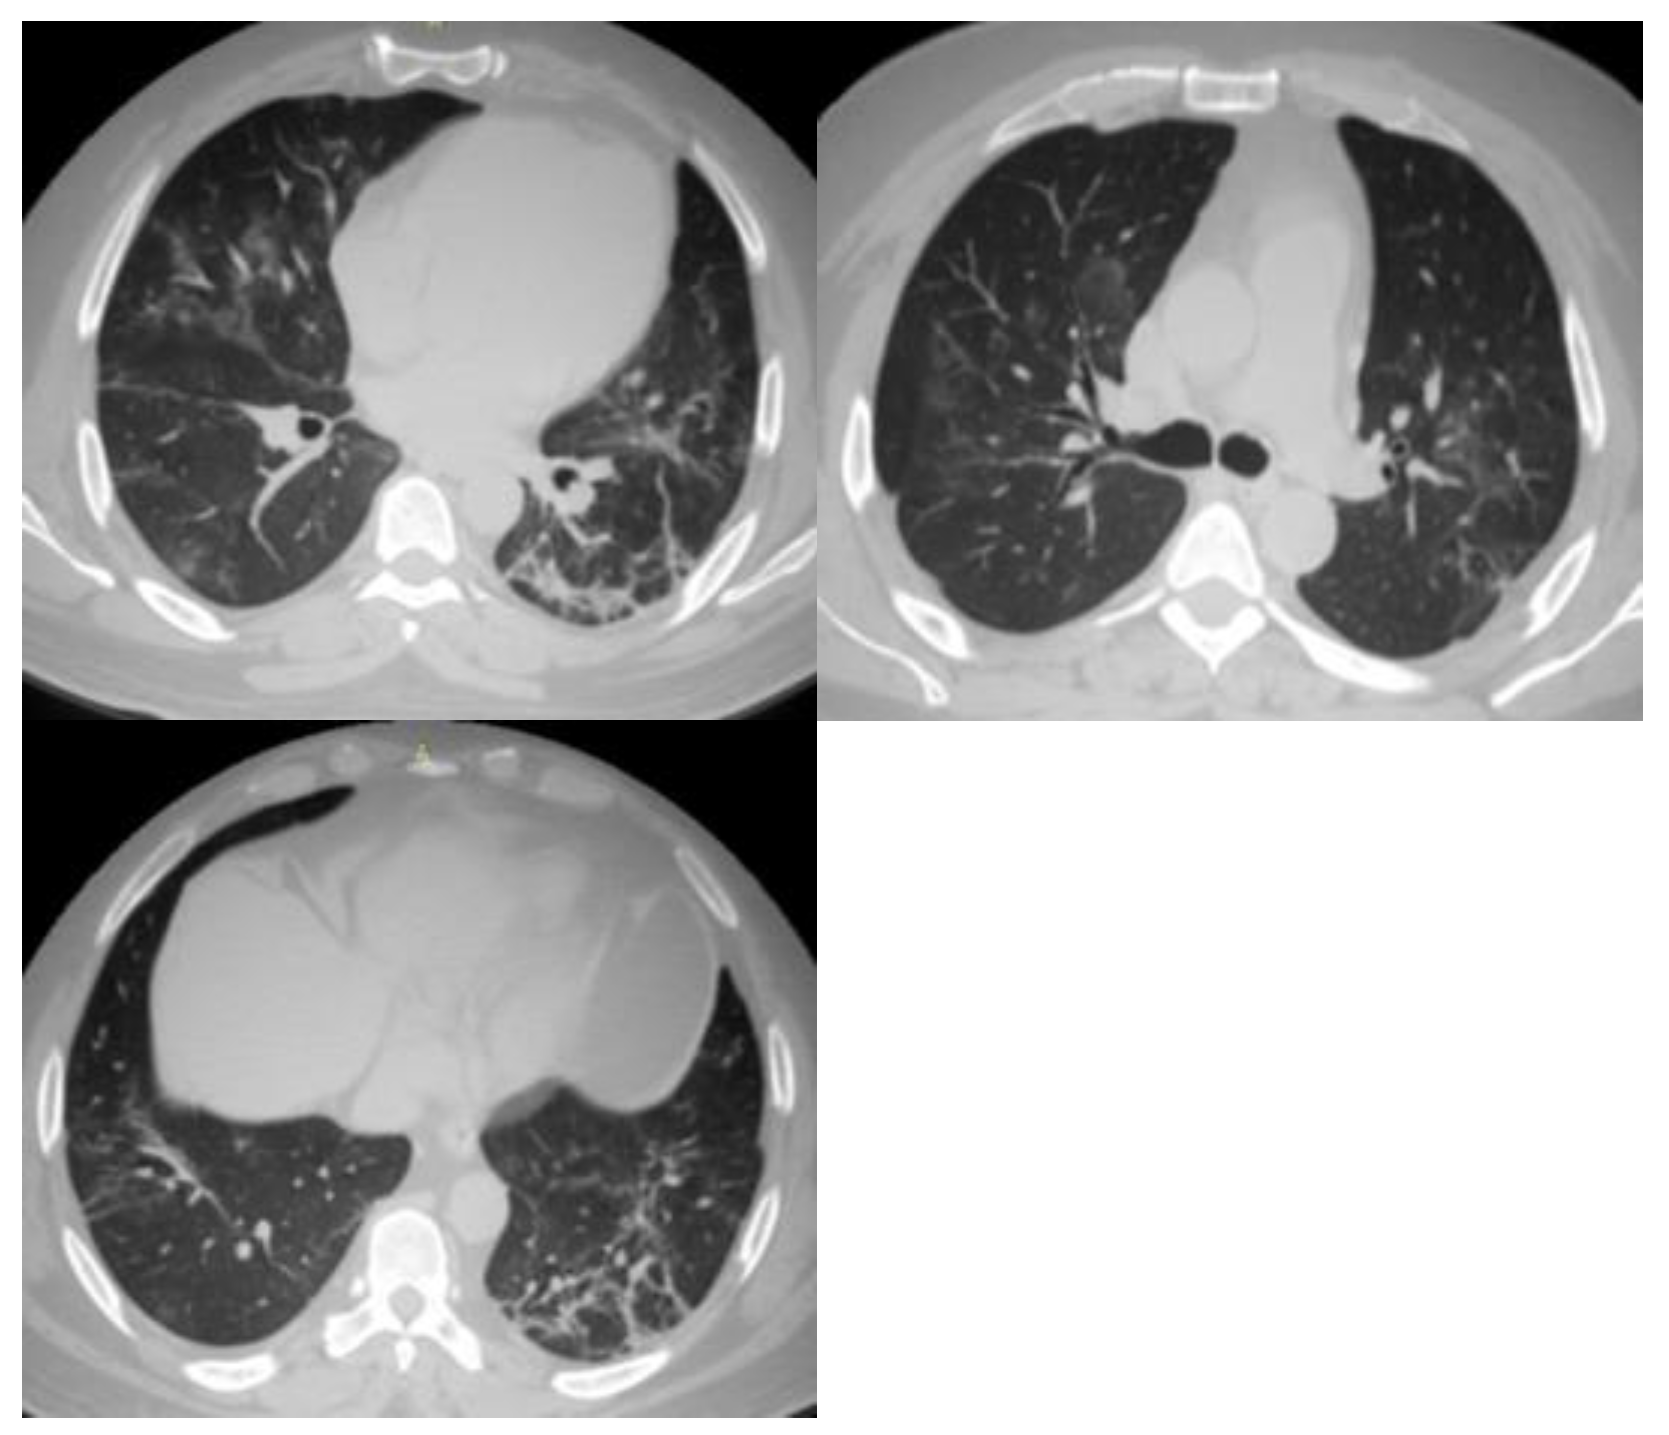

| 5 | Very high | Typical CT findings: ground-glass opacities with or without consolidations in lung regions close to visceral pleural surfaces and multifocal bilateral distribution. |